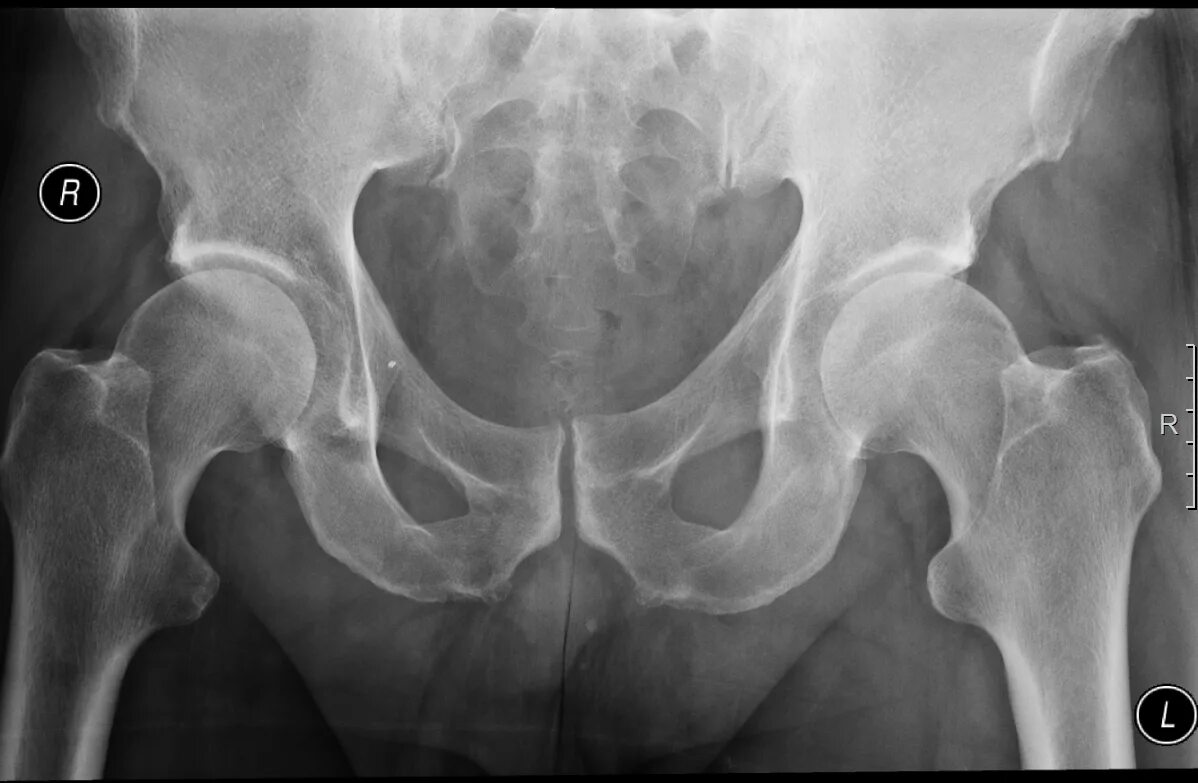

Коксартроз тазобедренного 1 стадии